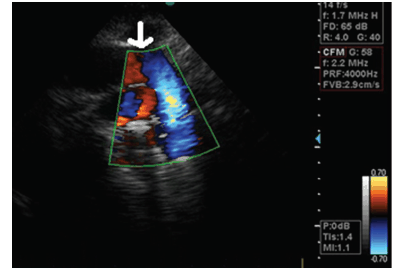

Na figura abaixo temos uma imagem de Doppler colorido ao nível do arco aórtico.

A parte negra situada entre o Doppler vermelho e o azul é resultante de: